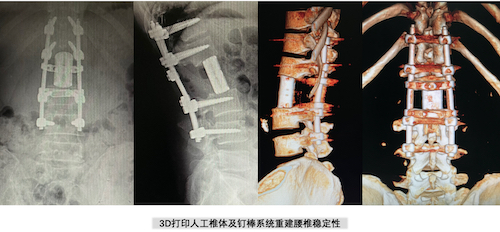

“手术难度很大,巨大的瘤体组织完全切除风险也很高,但我们一起接受挑战,争取给病人一次彻底治愈的机会。”脊柱肿瘤团队成员组织多次会诊,联合麻醉科、放射科、血管外科、泌尿外科等相关科室全面评估患者的病情特点,认为肿瘤病灶目前仅累及L2椎体,但腹膜后的占位病变压迫肾动脉,并可能累及一侧的L2和L3神经根,术中切除瘤体组织时可能导致肾动脉破裂导致难以控制的大出血,牺牲相应节段的神经根可能造成瘫痪。要实现彻底切除肿瘤,就必须同时完整切除L2椎体,并采用个体化定制的3D打印人工椎体重建脊柱的正常序列。

经过医院多学科会诊和讨论,确定好精确治疗方案后,3月8日,在麻醉、血管外、放射、泌尿外等多学科专家的配合下,邓幼文教授、臧晓方教授、苗惊雷副教授、陈世杰副教授、王卫国副教授和李劲松主治医师组成的手术医师团队,为李哥实施了后路L2椎体En-Bloc全切+巨大神经鞘瘤切除+椎管减压+人工椎体重建+钉棒系统内固定术。手术从早八点持续到下午七点,团队经过11个小时的奋战后,出血仅600mL,通过单次手术、单纯后入路将腰椎巨大肿瘤完整切除,同时右下肢功能得以完全保留。术后生命体征平稳,未出现任何手术相关并发症。